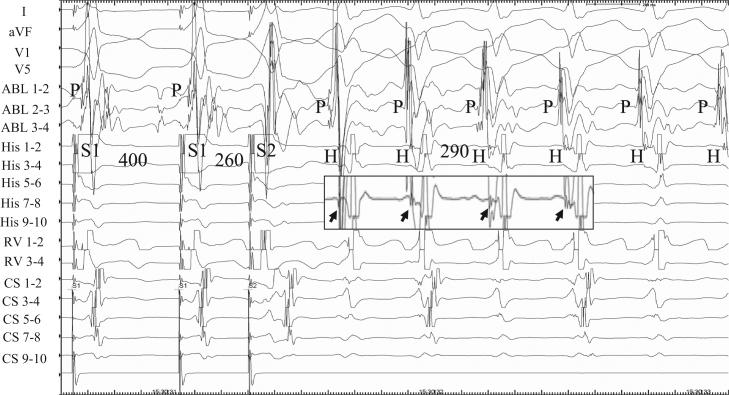

Role of the His bundle in verapamil-sensitive idiopathic left ventricular tachycardia.

HeartRhythm Case Rep. 2015 Mar 27;1(3):146-149. doi: 10.1016/j.hrcr.2015.03.011. eCollection 2015 May.